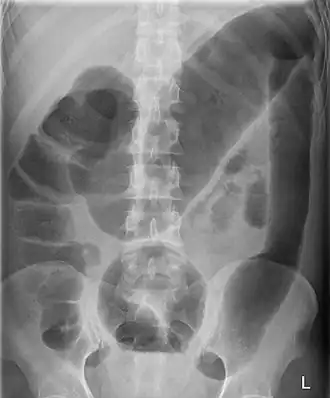

Colectasie ou mégacôlon visible sur un ASP dans le cadre d'une rectocolite hémorragique.

La colectasie (aussi appelée mégacôlon) est une dilatation massive du côlon gauche ou transverse, de plus de 6 cm, ou du cæcum de plus de 10 cm sans obstruction mécanique.

Elle se recherche à l'ASP (Abdomen Sans Préparation). Les facteurs prédisposants sont nombreux et peuvent être d'ordre traumatique (rachis, hématome abdominal, etc.), systémique (troubles électrolytiques, sepsis, iatrogénie, etc.), neurologique (affections médullaires), post-opératoires (vagotomie, césarienne, etc.), etc. Cet effet entraîne une altération de la mobilité colique entraînant les symptômes suivants :